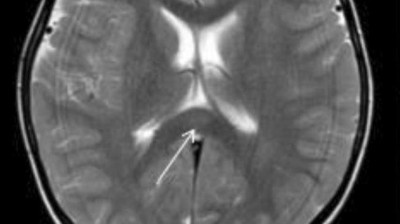

Brain Scans Predict Consciousness Return In Vegetative Patients

Absence Of Thirst In Association With Hydrocephalus Nejm